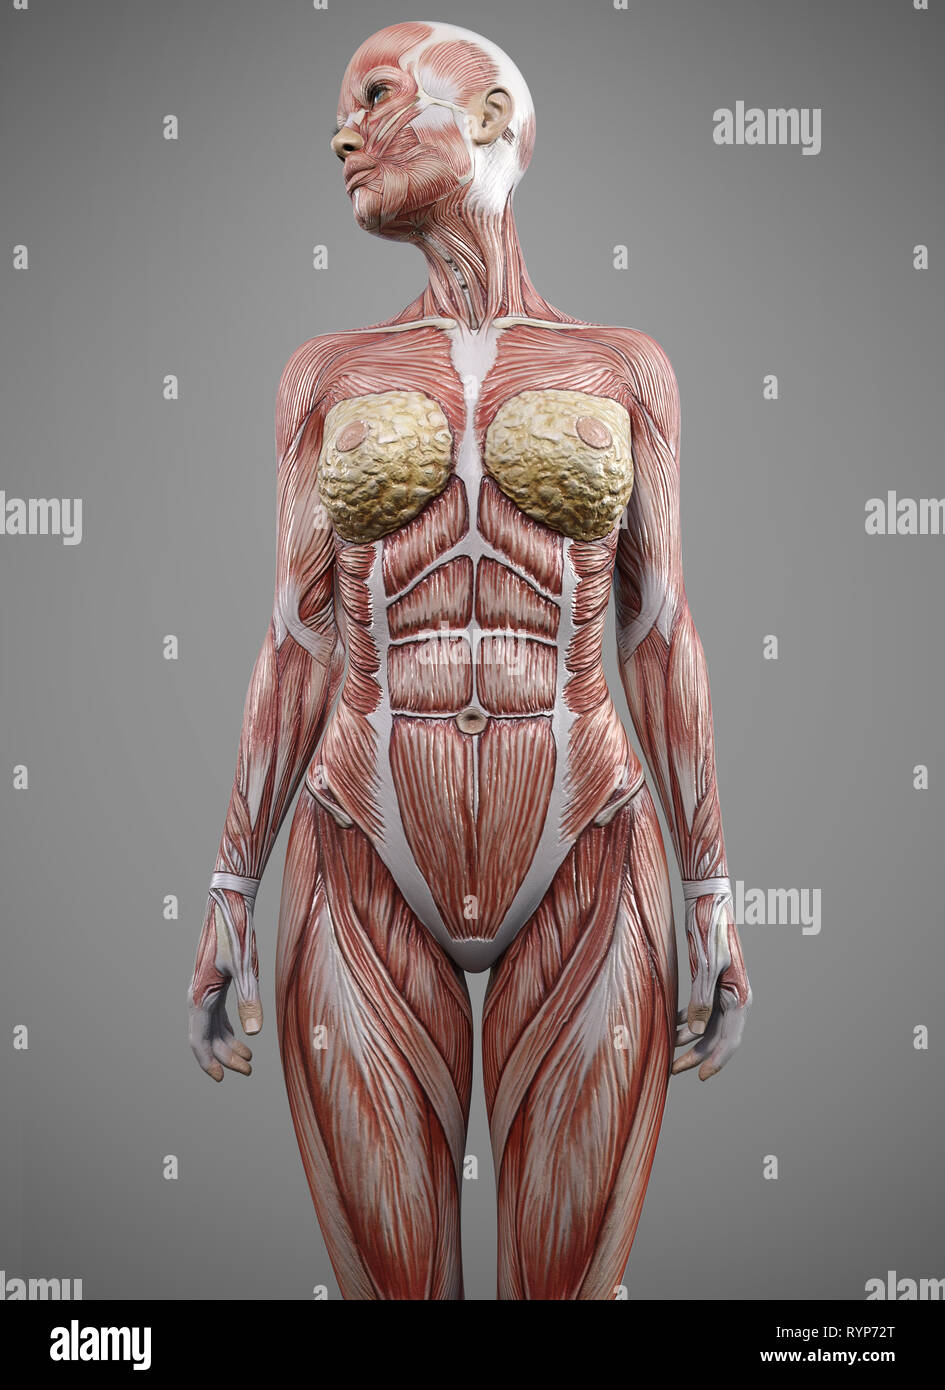

female muscle body anatomy - 3d rendering